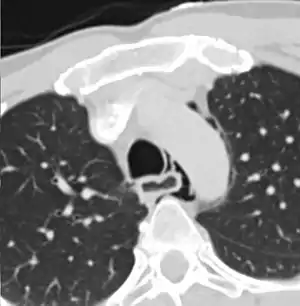

| Axial CT image through the upper chest showing extraluminal air (pneumediastinum) surrounding the trachea and esophagus | |

The diagnosis of Boerhaave's syndrome is suggested on the plain chest radiography and confirmed by chest CT scan. The initial plain chest radiograph is almost always abnormal in patients with Boerhaave's syndrome and usually reveals mediastinal or free peritoneal air as the initial radiologic manifestation. With cervical esophageal perforations, plain films of the neck show air in the soft tissues of the prevertebral space.

Hours to days later, pleural effusion(s) with or without pneumothorax, widened mediastinum, and subcutaneous emphysema are typically seen. CT scan may show esophageal wall edema and thickening, extraesophageal air, periesophageal fluid with or without gas bubbles, mediastinal widening, and air and fluid in the pleural spaces, retroperitoneum or lesser sac.